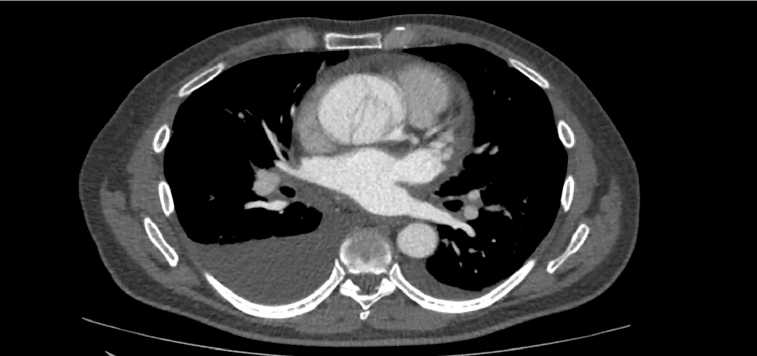

Рис. 4. СКТ-ангиография расслаивающей аневризмы грудного отдела аорты. Fig. 4. Computed tomography angiography demonstrating thoracic aortic dissection.

тре грудной аорты подозрение на расслоение — определялся двойной контур.

Учитывая данные эхокардиографии, выбрана тактика контролируемой гипотонии, также, несмотря на возраст, усилена терапия бета-адреноблокаторами, для контроля артериального давления начата инфузия урапидила со скоростью 10 мг/час после в/в введения 25 мг. Болевой синдром в грудной клетке удалось купировать на фоне удержания артериального давления (< 110/80 мм рт.ст.), частоты сердечных сокращений (< 65 уд/мин). После стабилизации состояния, для подтверждения диагноза пациент направлен на проведение СКТ-ангиографии грудной аорты с болюсным усилением, на которой выявили расслоение стенки восходящей части и дуги аорты (рис. 4) от аортального клапана до начальной части нисходящего отдела с формированием истинного и ложного просвета. Ложный просвет локально превосходил истинный более чем на 50% преимущественно на уровне восходящей аорты, диаметр истинного просвета на этом уровне — 15 мм, ложного — 30 мм.